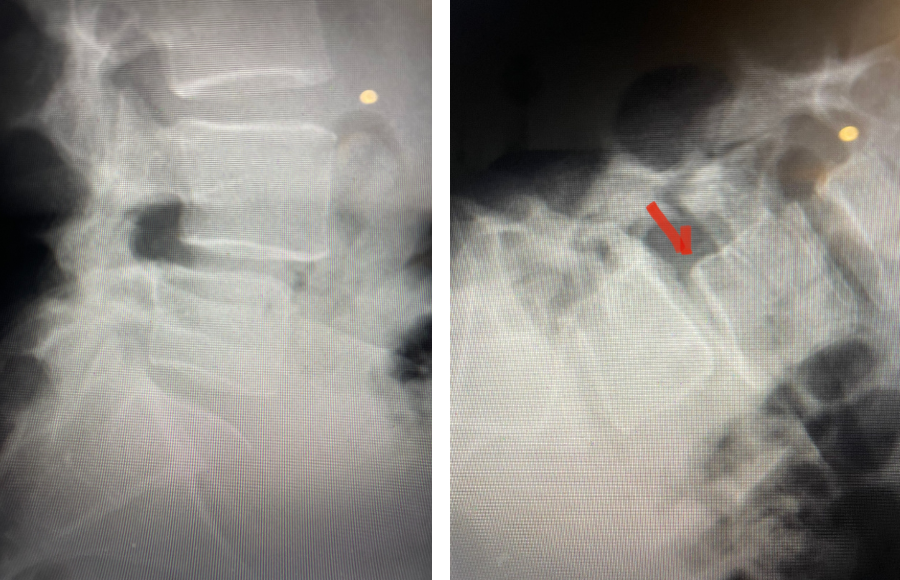

Fig 4: Sagittal and axial T2-weighted lumbar MRI images demonstrating severe next segment degeneration and stenosis at L2-3 above prior L3-5 fusion. Note retrolisthesis and significant facet arthropathy at L2-3 (red arrow).

Here is a dramatic example of a patient who had prior laminectomy and fusion surgery four years earlier, and now presents with low back pain with severe burning pain in her right lower extremity pain. She did not respond to epidural steroids. She had a prior L3-S1 laminectomy, and an L3-5 instrumented fusion. A current MRI (Fig 4) demonstrated severe L2-3 next segment stenosis due the development of massively hypertrophied or enlarged L2-3 joint complexes. There was also a grade 1 retrolisthesis of L2 on L3 with a large anterior disc osteophyte complex. The configuration of the stenosis was worse in the right lateral recess secondary to the anterior osteophyte and more right-sided facet compression of the thecal sac, correlating with the patient’s right-sided symptoms. When the anatomy correlates with the patient’s symptoms that is the best set up for success. It was decided to offer a revision surgery to the patient, who agreed.